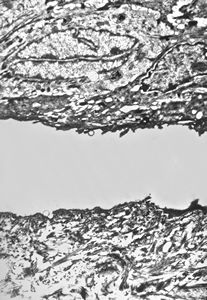

F, 41y. | epidermolysis bullosa … dystrophic type